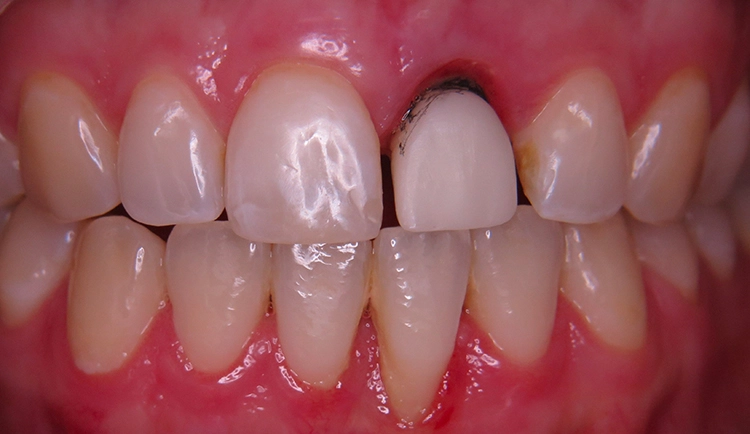

Die junge Patientin konsultierte die Zahnarztpraxis mit Beschwerden am Zahn 21. Der endodontisch vorbehandelte Zahn (multiple Wurzelspitzenresektionen) war mit einer Krone prothetisch versorgt (Abb. 1). Die Krone wirkte im Mund etwas dunkel und hatte einen grauen Schimmer. Da der Zahn zudem immer wieder Beschwerden bereitete, äußerte die Patientin den Wunsch nach einer Neuversorgung. Ansonsten war sie vollbezahnt und funktionell ohne pathologischen Befund. Parodontal zeigte sich eine kleine Rezession im Unterkiefer-Frontzahnbereich.

Zu den schwierigen Anforderungen im Frontzahnbereich gesellten sich hohe ästhetische Ansprüche. Die klinische sowie radiologische Diagnostik (Abb. 2) ergaben, dass der Versuch des Erhalts von Zahn 21 keine sichere Perspektive bot. Die Entscheidung fiel für die Extraktion des Zahnes. Um das Hart- und Weichgewebe bestmöglich vor der physiologischen Remodellierung nach der Extraktion zu bewahren, wurde eine Sofortimplantation geplant.